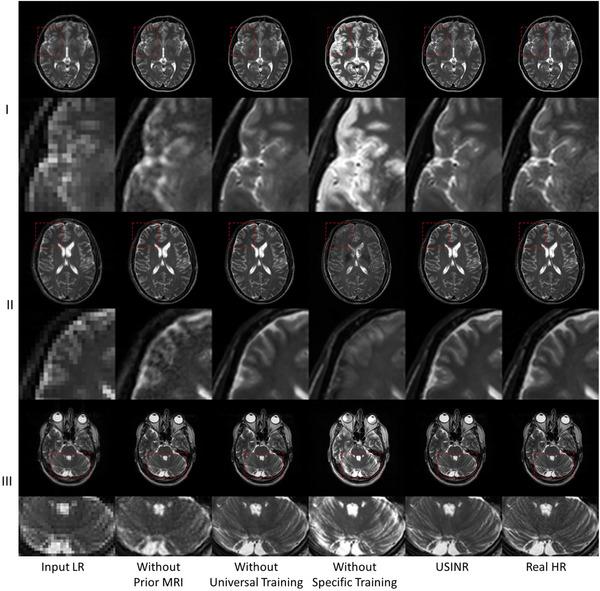

To achieve super-resolution for on-board MRI, this study proposed a universal anatomical mapping and patient-specific prior implicit neural representation (USINR) framework. Unlike traditional methods that interpolate solely based on individual on-board MR images, USINR can fully utilize the patient-specific anatomical information from a high-resolution prior MRI. In addition, USINR leverages knowledge about universal mapping between population-based prior MRIs and on-board MRIs, elevating the upper bound of super-resolution performance and enabling faster on-board fine-tuning.

USINR was evaluated on three datasets, including IXI, BraTS, and an in-house abdominal dataset. It achieved state-of-the-art performance on all of them. For example, on the BraTS dataset, USINR was trained on 1151 paired training samples (for universal anatomical mapping) and tested on 50 patients. It achieved average SSIM, PSNR, and LPIPS scores of 0.9656, 37.12, and 0.0214, respectively, significantly outperforming the published state-of-the-art method SuperFormer, whose corresponding scores were 0.9488, 35.83, and 0.0388. Furthermore, USINR can complete patient-specific training in less than one minute, rendering it a favorable solution in time-constrained ART workflows. In addition to large-scale dataset evaluations, a case study was conducted on an in-house patient at UT Southwestern Medical Center. This case study included two MRI scans (a prior scan for plan simulation and a new one for on-board imaging) from a single patient with a long interval between two scans, during which the tumor size underwent a significant change. Despite these substantial anatomical changes between prior and on-board imaging, USINR was able to accurately capture the change in tumor size, highlighting its robustness for clinical applications.

结果

USINR在三个数据集上进行了评估,包括IXI、BraTS和一个内部腹部数据集。在所有这些数据集上,它都取得了领先的性能。例如,在BraTS数据集上,USINR在1151对训练样本(用于通用解剖映射)上进行训练,并在50名患者上进行测试。它分别实现了平均结构相似性指数(SSIM)、峰值信噪比(PSNR)和学习感知图像补丁相似度(LPIPS)分数为0.9656、37.12和0.0214,显著优于已发表的领先方法SuperFormer,其相应分数分别为0.9488、35.83和0.0388。此外,USINR可以在不到一分钟的时间内完成患者特异性训练,使其成为时间受限的ART工作流程中的理想解决方案。除了大规模数据集评估外,还在德克萨斯大学西南医学中心的一名内部患者身上进行了案例研究。该案例研究包括来自一名患者的两次MRI扫描(一次用于计划模拟的先验扫描和一次用于机载成像的新扫描),两次扫描之间间隔较长,在此期间肿瘤大小发生了显著变化。尽管先验成像和机载成像之间存在这些显著的解剖结构变化,USINR仍能够准确捕捉肿瘤大小的变化,突出了其在临床应用中的稳健性。